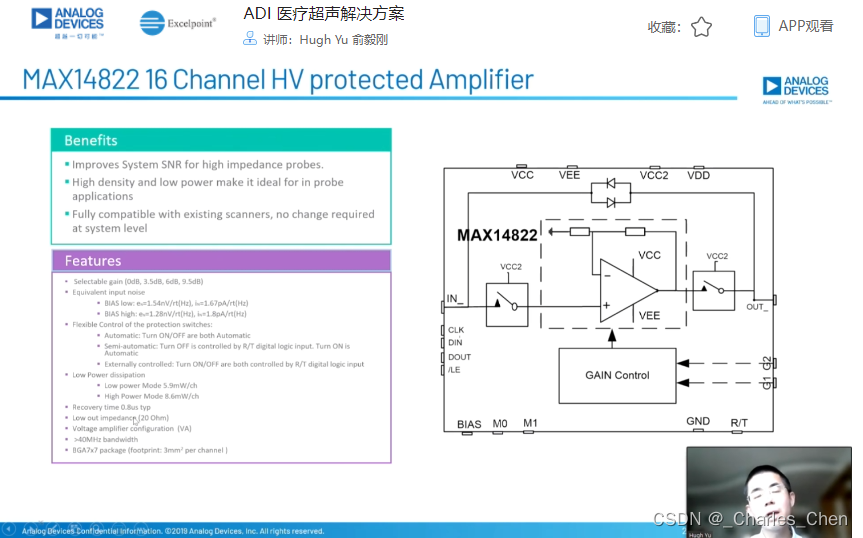

Tx/Rx开关

Tx/Rx开关可以保护低噪声放大器免受高压发射脉冲的影响,同时在接收间歇期间隔离低噪声放大器输入和发射机。该开关一般采用一组正确偏置的二极管阵列实现,当有高压发射脉冲出现时,它们会自动闭合或断开。Tx/Rx开关必须具备很快的恢复时间,以保证接收机在发射一个脉冲后能够立刻开启。这些快速恢复时间对于浅埋成像和提供低导通电阻确保接收灵敏度至关重要。

低噪声放大器(LNA)

接收机中的LNA必须具有出色的噪声性能和足够增益。对于设计合理的接收机,LNA将决定整个接收机的噪声性能。传感器单元通过较长的同轴电缆连接到相应的低阻抗LNA的输入端。如果没有适当的电缆终端匹配,电缆电容和传感器单元的源阻抗将大大制约从宽带传感器接收信号的带宽。传感器电缆匹配至低阻,有助于降低这一滤波的影响,有效提高图像质量。不幸的是,这种端接也降低了LNA的输入信号,因而降低接收灵敏度。由此可见,为LNA提供有源输入端接非常重要,可以在上述条件下提供必要的低输入阻抗端接和出色的噪声性能。